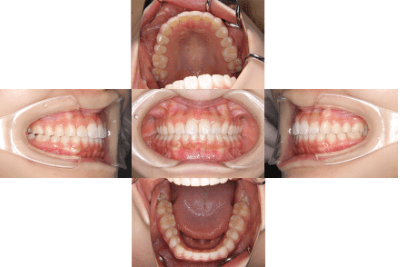

治療前

• 初診時年齢:16歳

• 主訴:叢生

• 診断:叢生を伴う骨格性I級症例、非抜歯

• 治療内容:顎が狭く、上の前歯が後ろに生えてしまい、ガタガタして上手く咬めない状態でした。幅を広くして、歯の角度を調整し、自然な位置に並べたので上手く咬めるようになりました。

• 治療期間:2年

• リスク:ブラックトライアングル(歯と歯の間と歯ぐきの間の三角形の隙間)が強くでる場合がある

• 費用:90万円